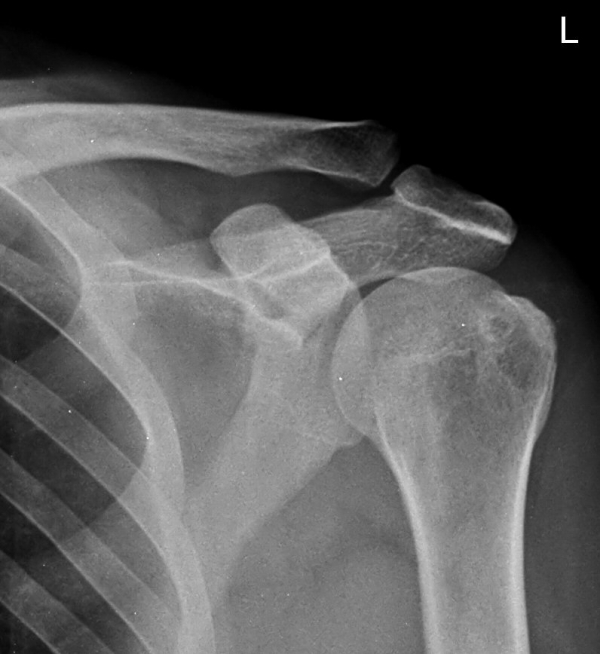

ƯÀÌ °ßºÀ ¾Æ·§¸éÀÇ °æÈ­ ¼Ò°ß ¹× °ßºÀ ¾Æ·¡ ¿¹¸®ÇÑ °ñ±ØÀÌ °üÂûµÊ